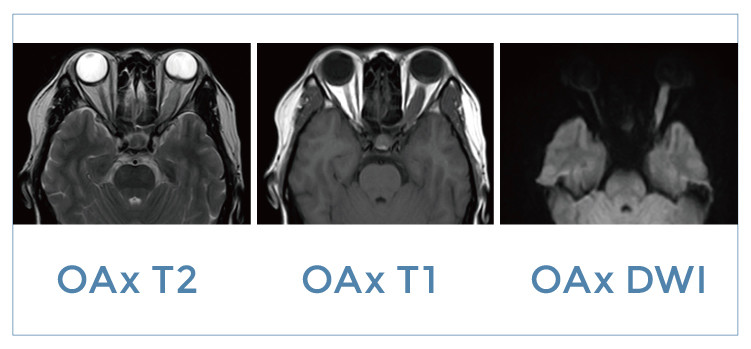

【朗润影像档案】20191101磁共振影像病例结果讨论

【朗润影像档案】磁共振影像病例分享(编号20191101)